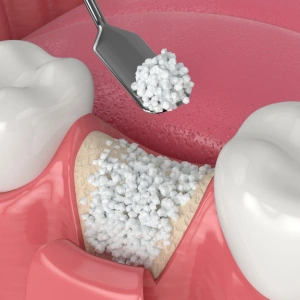

Bone Grafting

Bone grafting is a regenerative procedure used when gum disease has caused loss of supporting bone around your teeth. Our gum specialist dentist rebuilds the lost bone using biocompatible materials, helping restore stability and support for implants or natural teeth.

Benefits:

- Restores lost bone and strengthens jaw support

- Helps save teeth affected by gum disease

- Improves chances of successful dental implants

- Enhances facial structure and chewing ability

- Prevents further bone deterioration